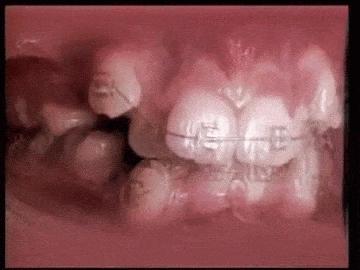

#5会感觉有橡皮筋在你口中

那是真的!他就像是几千条橡皮筋,把你两排的牙齿结合起来。